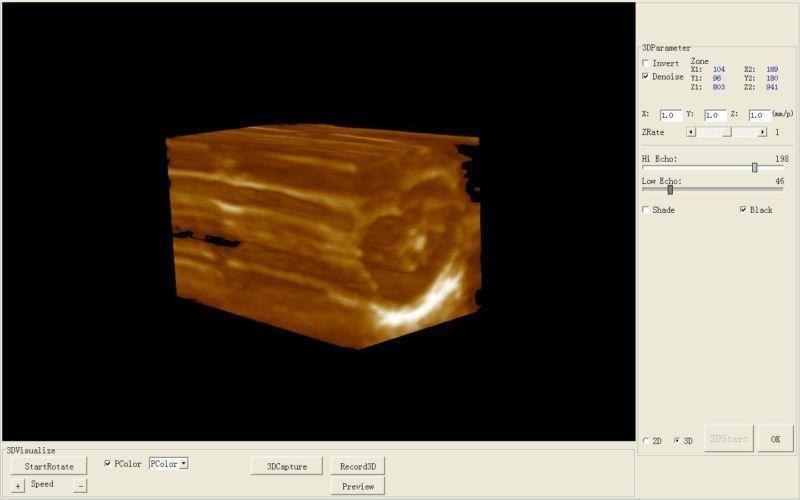

Model: HIGH RESOLUTION

Frame correlation: selectable 4 levels

Display modes: B, B+B, B+M, M, 4B

Pseudo color processor: 7 colors

Scanner depth: 230mm

Gray scale: 256

Image conversion: up/down, left/right, black/white

Local zoom: 4(can be used at frozen/real-time)